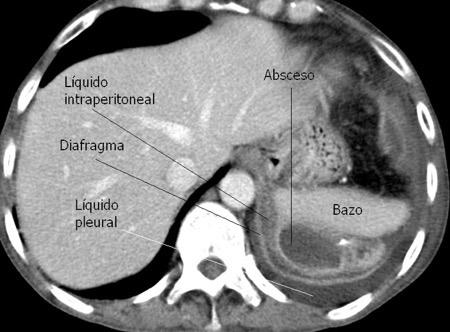

39. EMPIEMA DE ORIGEN SUBDIAFRAGMÁTICO

40. EMPIEMA PLEURAL. ORIGEN HEPÁTICO

Naidich DP et al. Computed tomography of the diaphragm: peridiaphragmatic fluid localization.J Comput Assist Tomogr1983.

En el corte axial, el líquido pleural se sitúa por detrás

Colecciones “inflamatorias” abdominales llegan al tórax vía el hiato esofágico o por vía transdiafragmática

Afectación transdiafragmática: 5,6-43,7% de quistes hepáticos. “Área desnuda” del hígado.

Panda A et al. “Straddling Across Boundaries”. Thoracoabdominal Lesions: Spectrum and Pattern Approach. Curr Probl Diagn Radiol. 2015 Área desnuda. El hígado en contacto directo con el tendón central del diafragma. Contiene el hiato de VCI.